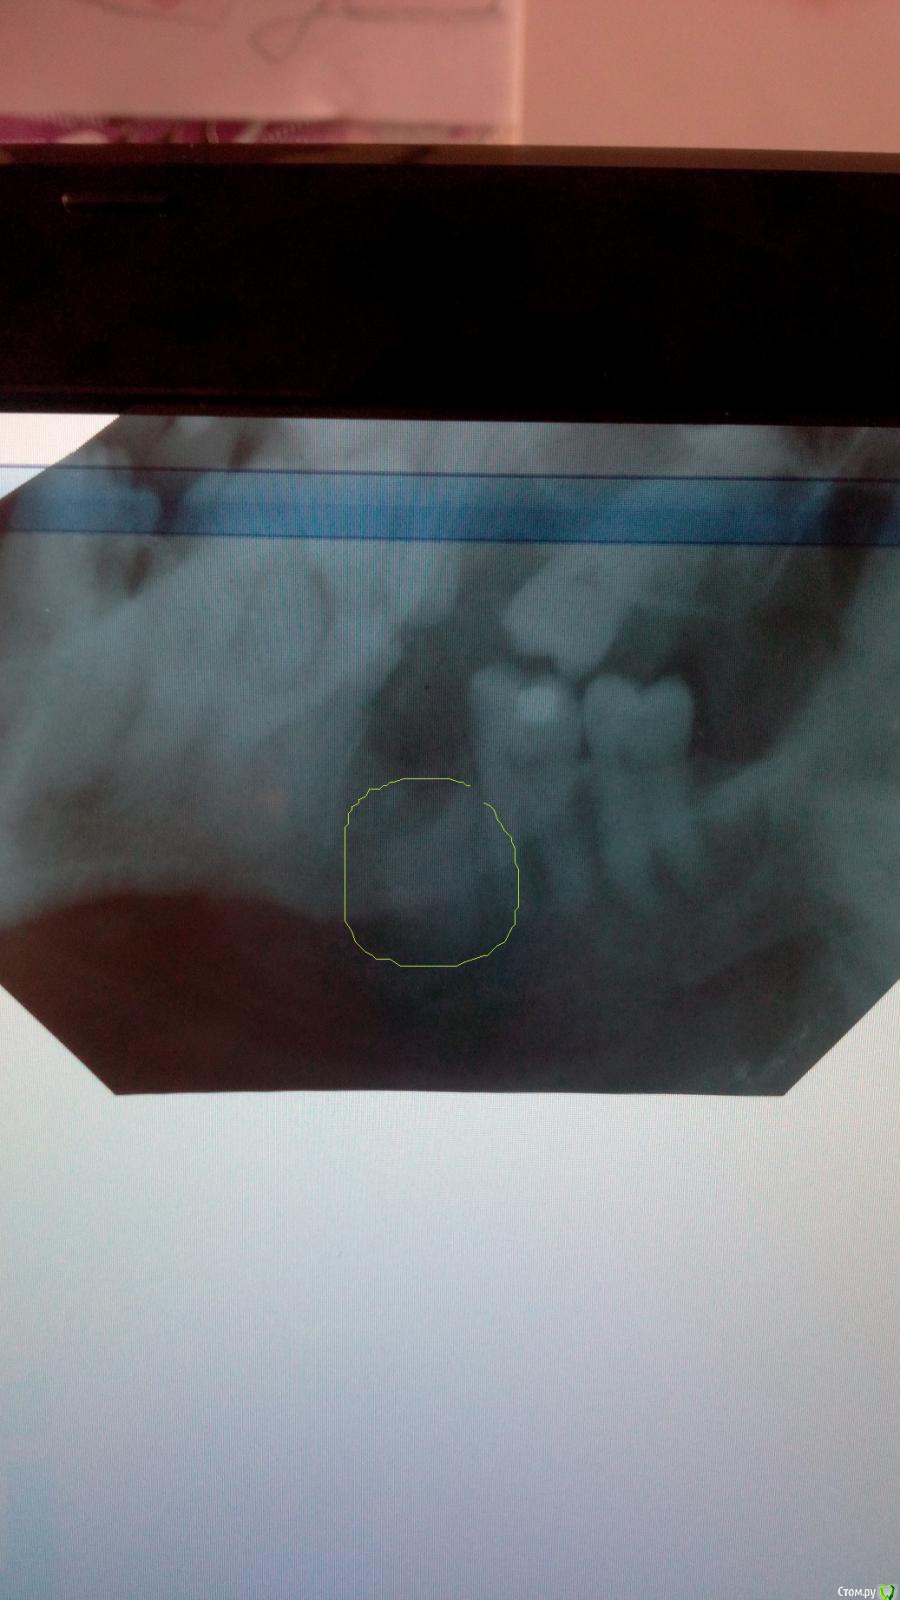

денис228 Опубликовано 12 мая, 2015 Поделиться Опубликовано 12 мая, 2015 примерно неделю были ноющие боли,потом прошли сходил в поликлинику сделали снимок сказали что осколок большой оставили(удалял в платной клинике)сходил туда где удалял врач сказал что все нормально не какого осколка нет и все хорошо заживает(кому и верить)десну больно трогать и лунка еще не затянулась.Помогите разобраться пожалуйста. Ссылка на комментарий

molchanoff Опубликовано 12 мая, 2015 Поделиться Опубликовано 12 мая, 2015 качество снимка не очень, но вроде что-то есть там.новый снимок в студию 1 Ссылка на комментарий

Bier Опубликовано 12 мая, 2015 Поделиться Опубликовано 12 мая, 2015 сделайте новый снимок, нормальный на визиографе. Но судя по всему корень там есть. Ссылка на комментарий